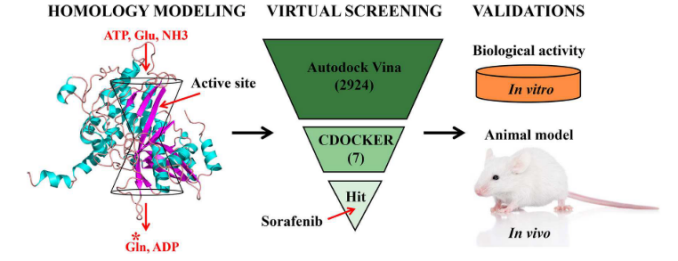

4.3.3 虚拟筛选

4.3.3 虚拟筛选

虚拟筛选(Virtual Screening)是一种在计算机上进行的药物发现方法,它通过计算方法来预测哪些化合物可能与特定的生物靶点有活性。这个方法通常用于处理大规模的化合物库,以便在实验室进行实验之前筛选出最有可能有效的化合物。

虚拟筛选可以分为两大类:基于结构的虚拟筛选和基于配体的虚拟筛选。

基于结构的虚拟筛选(Structure-Based Virtual Screening):这种方法需要知道靶点的三维结构。通过计算化合物与靶点的结合能或者得分,预测化合物对靶点的亲和力。常用的方法有分子对接(Molecular Docking)等。

基于配体的虚拟筛选(Ligand-Based Virtual Screening):这种方法不需要知道靶点的三维结构,只需要已知活性配体的信息。通过比较候选化合物与已知活性配体的相似性,预测化合物的活性。常用的方法有分子指纹比较(Molecular Fingerprint Comparison)等。

在分子动力学模拟中,虚拟筛选通常用于预测化合物与靶点的动态相互作用,以及化合物在体内的动态行为,例如代谢稳定性和毒性等。